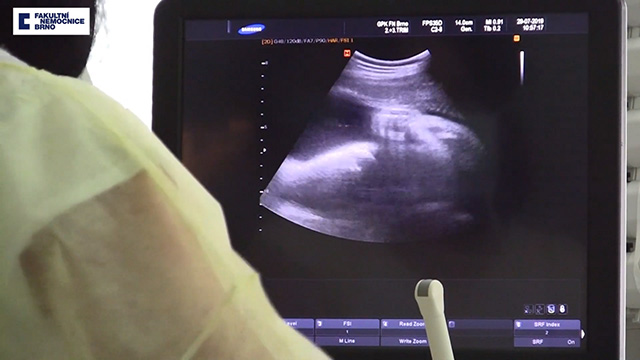

Câu chuyện cảm động này xảy ra ở Cộng Hòa Séc. Người mẹ này đã bị chết não khi đang mang thai đứa con của mình. Các bác sĩ đã duy trì sự sống cho cô gần 4 tháng để sinh hạ đứa trẻ.

Theo trang New Straits Times, vào ngày 15.8 vừa qua, một bé gái được sinh ra tại bệnh viện Đại học Brno, nặng 2,13kg và cao 42cm. Người mẹ được xác định là đã chết não vào tháng 4, sau khi bị xuất huyết lúc mang thai được 16 tuần.

Các bác sĩ đã hỗ trợ cho người mẹ này cuộc sống nhân tạo nhằm giữ cho tim, phổi, thận và các cơ quan khác còn hoạt động trong khi theo dõi thai nhi. Trong suốt thai kỳ, bác sĩ siêu âm thường xuyên và làm các động tác như là người mẹ đang đi bộ, nhằm giúp em bé trong bụng phát triển bình thường.